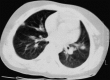

Severe acute respiratory syndrome (SARS) is a newly recognised and highly contagious respiratory infection caused by a new strain of coronavirus. The disease can result in progressive respiratory failure in adults and the mortality rate has been reported to be 8-15%. This infection spreads by droplet transmission and children appear to acquire SARS through close household contact exposure to infected adults. Disease severity is, however, much milder in the paediatric age group. The common laboratory findings in infected children and adolescents include lymphopaenia and elevated levels of lactate dehydrogenase and creatinine phosphokinase. Air space consolidation is commonly seen during the course of the illness although chest radiographs are normal on presentation in half of the cases. The pathophysiology of SARS appears to be related to immunological dysregulation in response to the coronavirus infection. The optimal treatment of SARS in children remains to be determined. No case fatality in infected children has been reported. The early and proper isolation of infected adults, meticulous infection control measures in the hospital setting, exhaustive contact tracing and quarantine measures are important steps in preventing the spread of the disease among health care workers and into the community. The development of a sensitive and rapid test for early diagnosis is underway. Further controlled trials are necessary to define the optimal treatment of this infection in children.